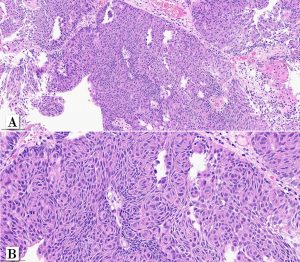

A male patient in his early 70s underwent surgical removal a single pedunculated 3 cm polypoid tumor in the bladder mucosa at the left lateral wall.

Papillary urothelial carcinoma, noninvasive, whorled subtype

One rare morphologic subtype of in noninvasive papillary urothelial carcinoma has been described as a whorled pattern. Patriarca et al. 2014 described a series of 12 patients: all noninvasive and most of them 11/12 classified as low-grade. One patient had a tumor with mixed grade (5% of the tumor at other areas. Whorled pattern shows concentrically organized cell structures, without morphological evidence of keratinization, similar to the whorling structures of transitional meningioma.

In that series, none of the cases experienced T1 stage progression and two recurrences occurred. One of the recurrent tumors was the one harboring small focus of high-grade tumor inside the primary lesion. Interestingly, the recurrent cases maintained the same whorling pattern in the second transurethral resection specimens. Therefore, although limited data on follow up is available, clinical behavior seems to be similar to low-grade noninvasive papillary urothelial carcinoma (Patriarca et al. 2014). Awareness of this morphologic subtype is important to avoid misclassification of other epithelial lesions which may show squamous or squamoid morphology.